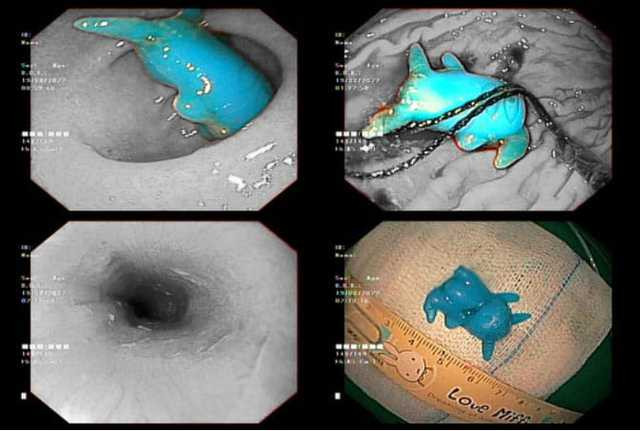

Bệnh viện Nhi đồng 2 TP.HCM vừa nội soi cấp cứu lấy dị vật là đồ chơi pikachu bằng nhựa, kích thước 2x2, 5x1cm, bị kẹt ở thực quản cho bệnh nhi 6 tuổi. Hình thù đồ chơi có sừng dài dễ đâm lủng thực quản và gây khó khăn trong quá trình xử trí.

Dị vật là đồ chơi pikachu bằng nhựa, có kích thước 2x2, 5x1cm.